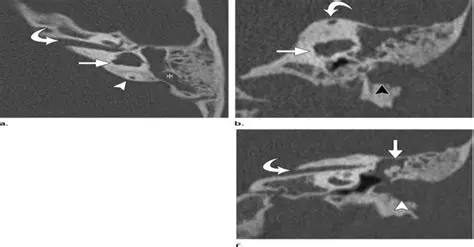

Observation of External Malformations